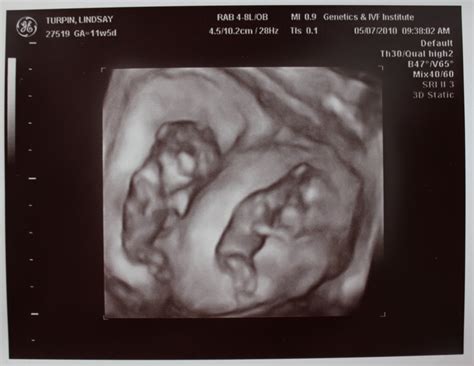

• baby at 12 weeks ultrasound

• baby at 12 weeks pics